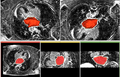

Magnetic resonance imaging (MRI) has been used for both pre- and and post-ablation assessment of the atrial wall. MRI can aid in selecting the right candidate for the ablation procedure and assessing post-ablation scar formations. Image processing techniques can be used for automatic segmentation of the atrial wall, which facilitates an accurate statistical assessment of the region. As a first step towards the general solution to the computer-assisted segmentation of the left atrial wall, in this research we propose a shape-based image segmentation framework to segment the endocardial wall of the left atrium.

We are developing methods to segment the left atrial wall in delayed-enhanced MR imagery.